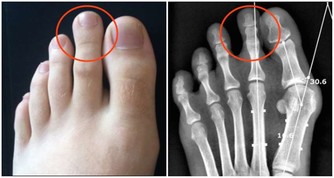

*****6.轉移灶的疼痛*****

肝癌會轉移到其他部位,比如轉移到肺部、骨骼處、那麼就可能出現骨痛、胸痛的情況。